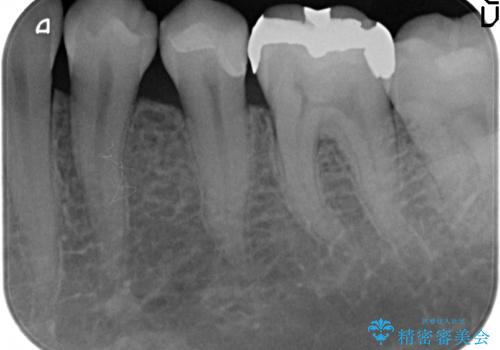

セラミックインレー 他院にて歯の神経治療が必要と言われた虫歯

自発痛・持続痛等の症状がなく、露髄(歯の神経が露出してしまうこと)することなく虫歯の除去を完了したため、しばらく経過観察を行った後に神経治療をすることなく、セラミックインレーによる修復を行うことができました。

当院のセラミックインレーはemaxという強度と審美性に優れた材料を使用しています。

またプレス方式でインレーを製作しているため、削り出しで製作するCADCAMより優れた適合性も持ち合わせており、虫歯が再発しにくい修復物です。